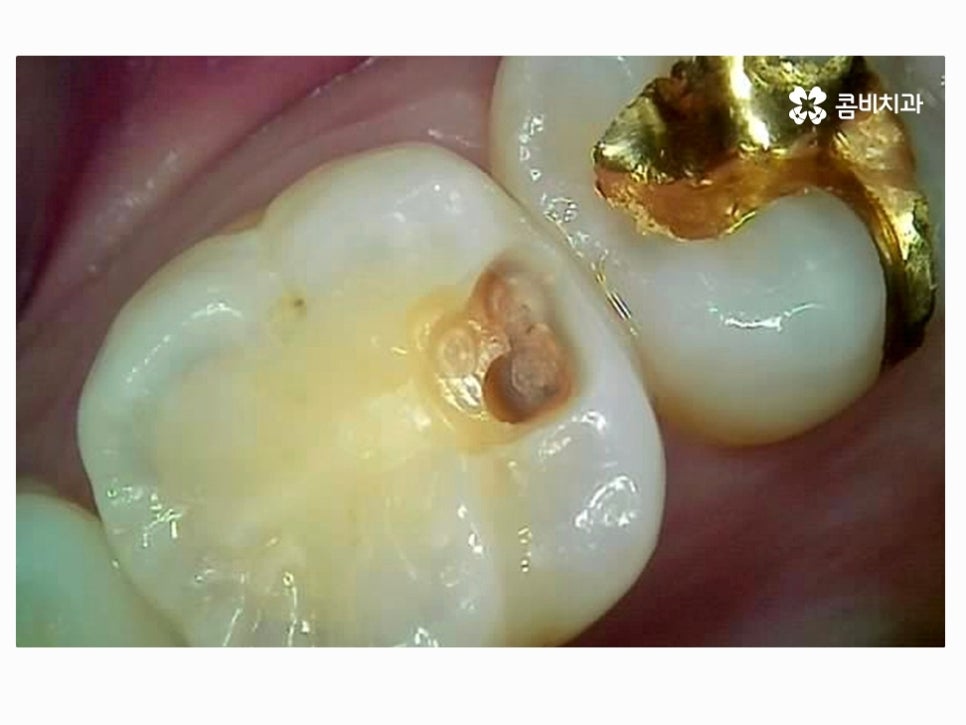

마지막으로 소개드릴 사례 역시도 이미 크라운을 씌웠던 치아 내부가

심하게 썩어서 잇몸 치료와 함께 지르코니아 크라운을 다시 씌운 사례라고 할 수 있어요.

이러한 사례처럼 이미 기존 치아의 형태가 심하게 손상이 된 경우에는

치료가 쉽지 않고 발치로 이어지는 경우도 많지만 환자분 들께서도

대부분 자연치아를 살리길 원하시고 명동치과 의사의 입장에서도

되도록 자연치아를 되도록 오래 쓰실 수 있도록 도와드리고 있는데요.

기존의 치아를 최대한 살려도 치료 후 수명이 오래가지 못할 것으로

예상이 된다거나 어쩔 수 없이 발치를 할 수밖에 없는 상황도

있기 때문에 나이가 들수록 치아 검진 습관을 더욱 강조되고 있어요.

다행히도 사진의 환자분께서는 내부 충치를 잘 제거하고

다시 지르코니아 크라운을 씌워서 치료를 안전하게 마칠 수 있었지만